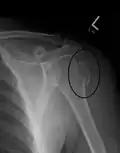

A fracture of the greater tuberosity as seen on AP X ray -

A fracture of the greater tuberosity of the humerus -

Fracture of the greater tuberosity of the humerus -